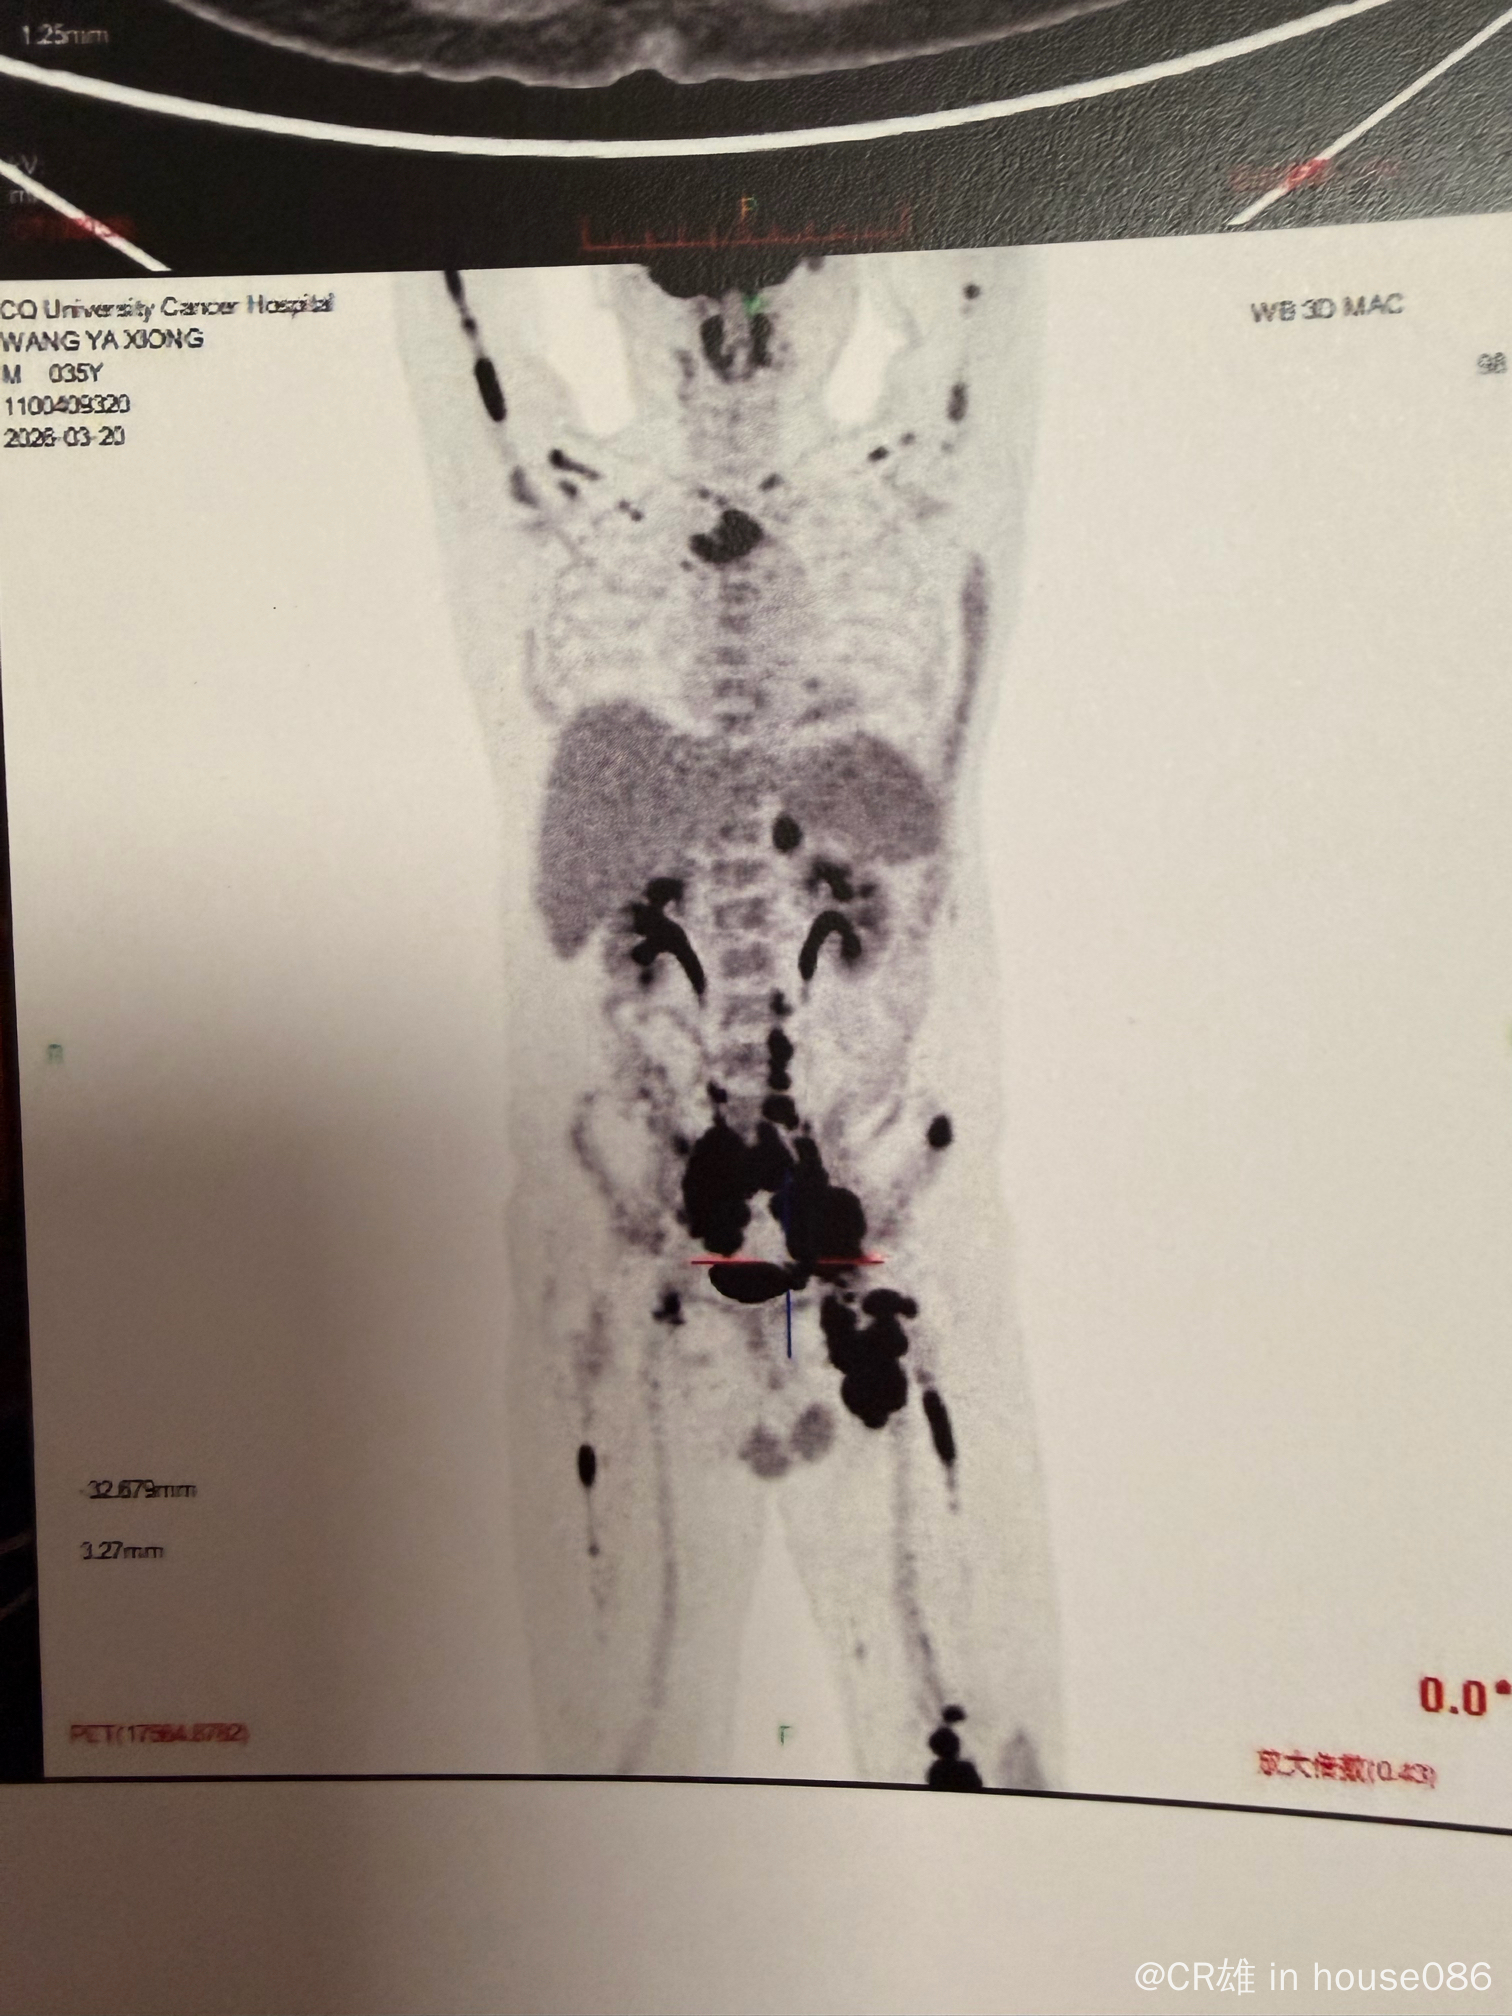

弥漫大B,IV期,骨髓侵犯,GCB型,伴CD5+,myd88和CD79b变异

petCT显示很多地方都累及

骨穿报告显示累及骨髓